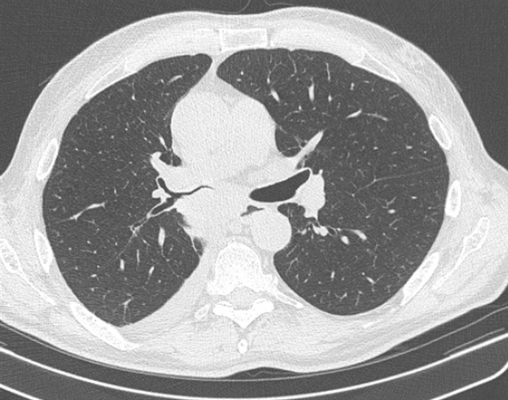

Периферический рак постепенно сформировывается в боковых отделах легких, медленно прорастая и ничем себя не обнаруживая. Данная опухоль легкого симптомы долгое время может не давать, они появляются при значительном местном распространении, вовлечении соседних органов и структур, прорастания бронхов. Диагностика рака легких этого типа локализации чаще всего возможна при профилактическом обследовании (рентгенографии или компьютерной томографии).

Фото 2 — Периферический рак (1) верхней доли правого легкого